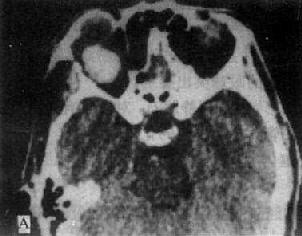

(一)眶内肿瘤 CT对确定眶内肿瘤的存在、位置、大小、范围和区别良性与恶性比较可靠。良性肿瘤表现为边缘清楚、光滑、密度均匀的高密度肿块(图5-2-2A)。而囊肿则为边缘清楚圆形低密度区。靠近眶壁时可出现凹窝,外围以硬化带。恶性肿瘤形态不规则,密度不均匀,边界也不清楚,常有眶骨破坏,并向颅内、鼻窦延伸。这些对恶性肿瘤的诊断有一定帮助。由鼻窦、颅内或眶骨肿瘤向眶内延伸,CT发现肿瘤主要部分在眶外,而眶内部分较小,有助于肿瘤起源的判断。对肿瘤病理性质的判断困难。

图5-2-2 眼眶CT扫描

左眼眶内血管瘤,肿瘤边缘清楚、光滑,均匀性显著强化